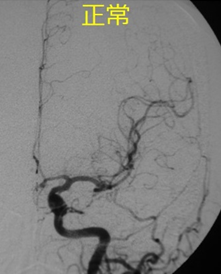

脳血管障害は大人に多い疾患ですが、小児でも脳梗塞や脳出血、くも膜下出血を起こすことがあります。代表的な小児脳血管障害であるもやもや病についてご紹介します。

もやもや病とは、脳の血管が進行性に狭窄する原因不明の疾患です。その付近に側副血行路が発達して脳血管撮影検査でもやもやと描出されるため、もやもや病と名付けられています。

治療としては、脳血流が著しく不足している場合には血行再建術を行います。術式にはいろんなバリエーションがあります。大きく分けて、①直接的血行再建術(浅側頭動脈(STA)-中大脳動脈(MCA)バイパス術など)と、②間接的血行再建術(浅側頭動脈、側頭筋、骨膜などを脳表に接着させ血管新生を促すもの)があります。当科では患者さんの病態や重症度に応じて、①のみ、②のみ、①と②の組み合わせなど様々な治療を行なっています。